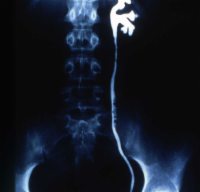

Die ausgedehnte retroperitoneale LK-Metastasierung (Bulky disease) eines Hodentumors (Embryonalkarzinom und Seminom) mit Ummauerung der großen Gefäße (Aorta und Vena cava) sowie des linksseitigen Nierengefäßstieles führte bei dem jungen Mann zu einer vasculär bedingten Schrumpfung der linken Niere (Abbildung 18a,e) (

s. Tumoren/Hoden).

In der Sonographie fand sich eine kleine Niere links bei unauffälliger rechter Niere (Abbildung 18b).